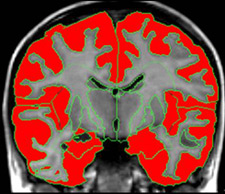

Yellow region of brain shows the enlarged white matter of an autistic brain. The red regions show the grey matter which is smaller in autistic children.